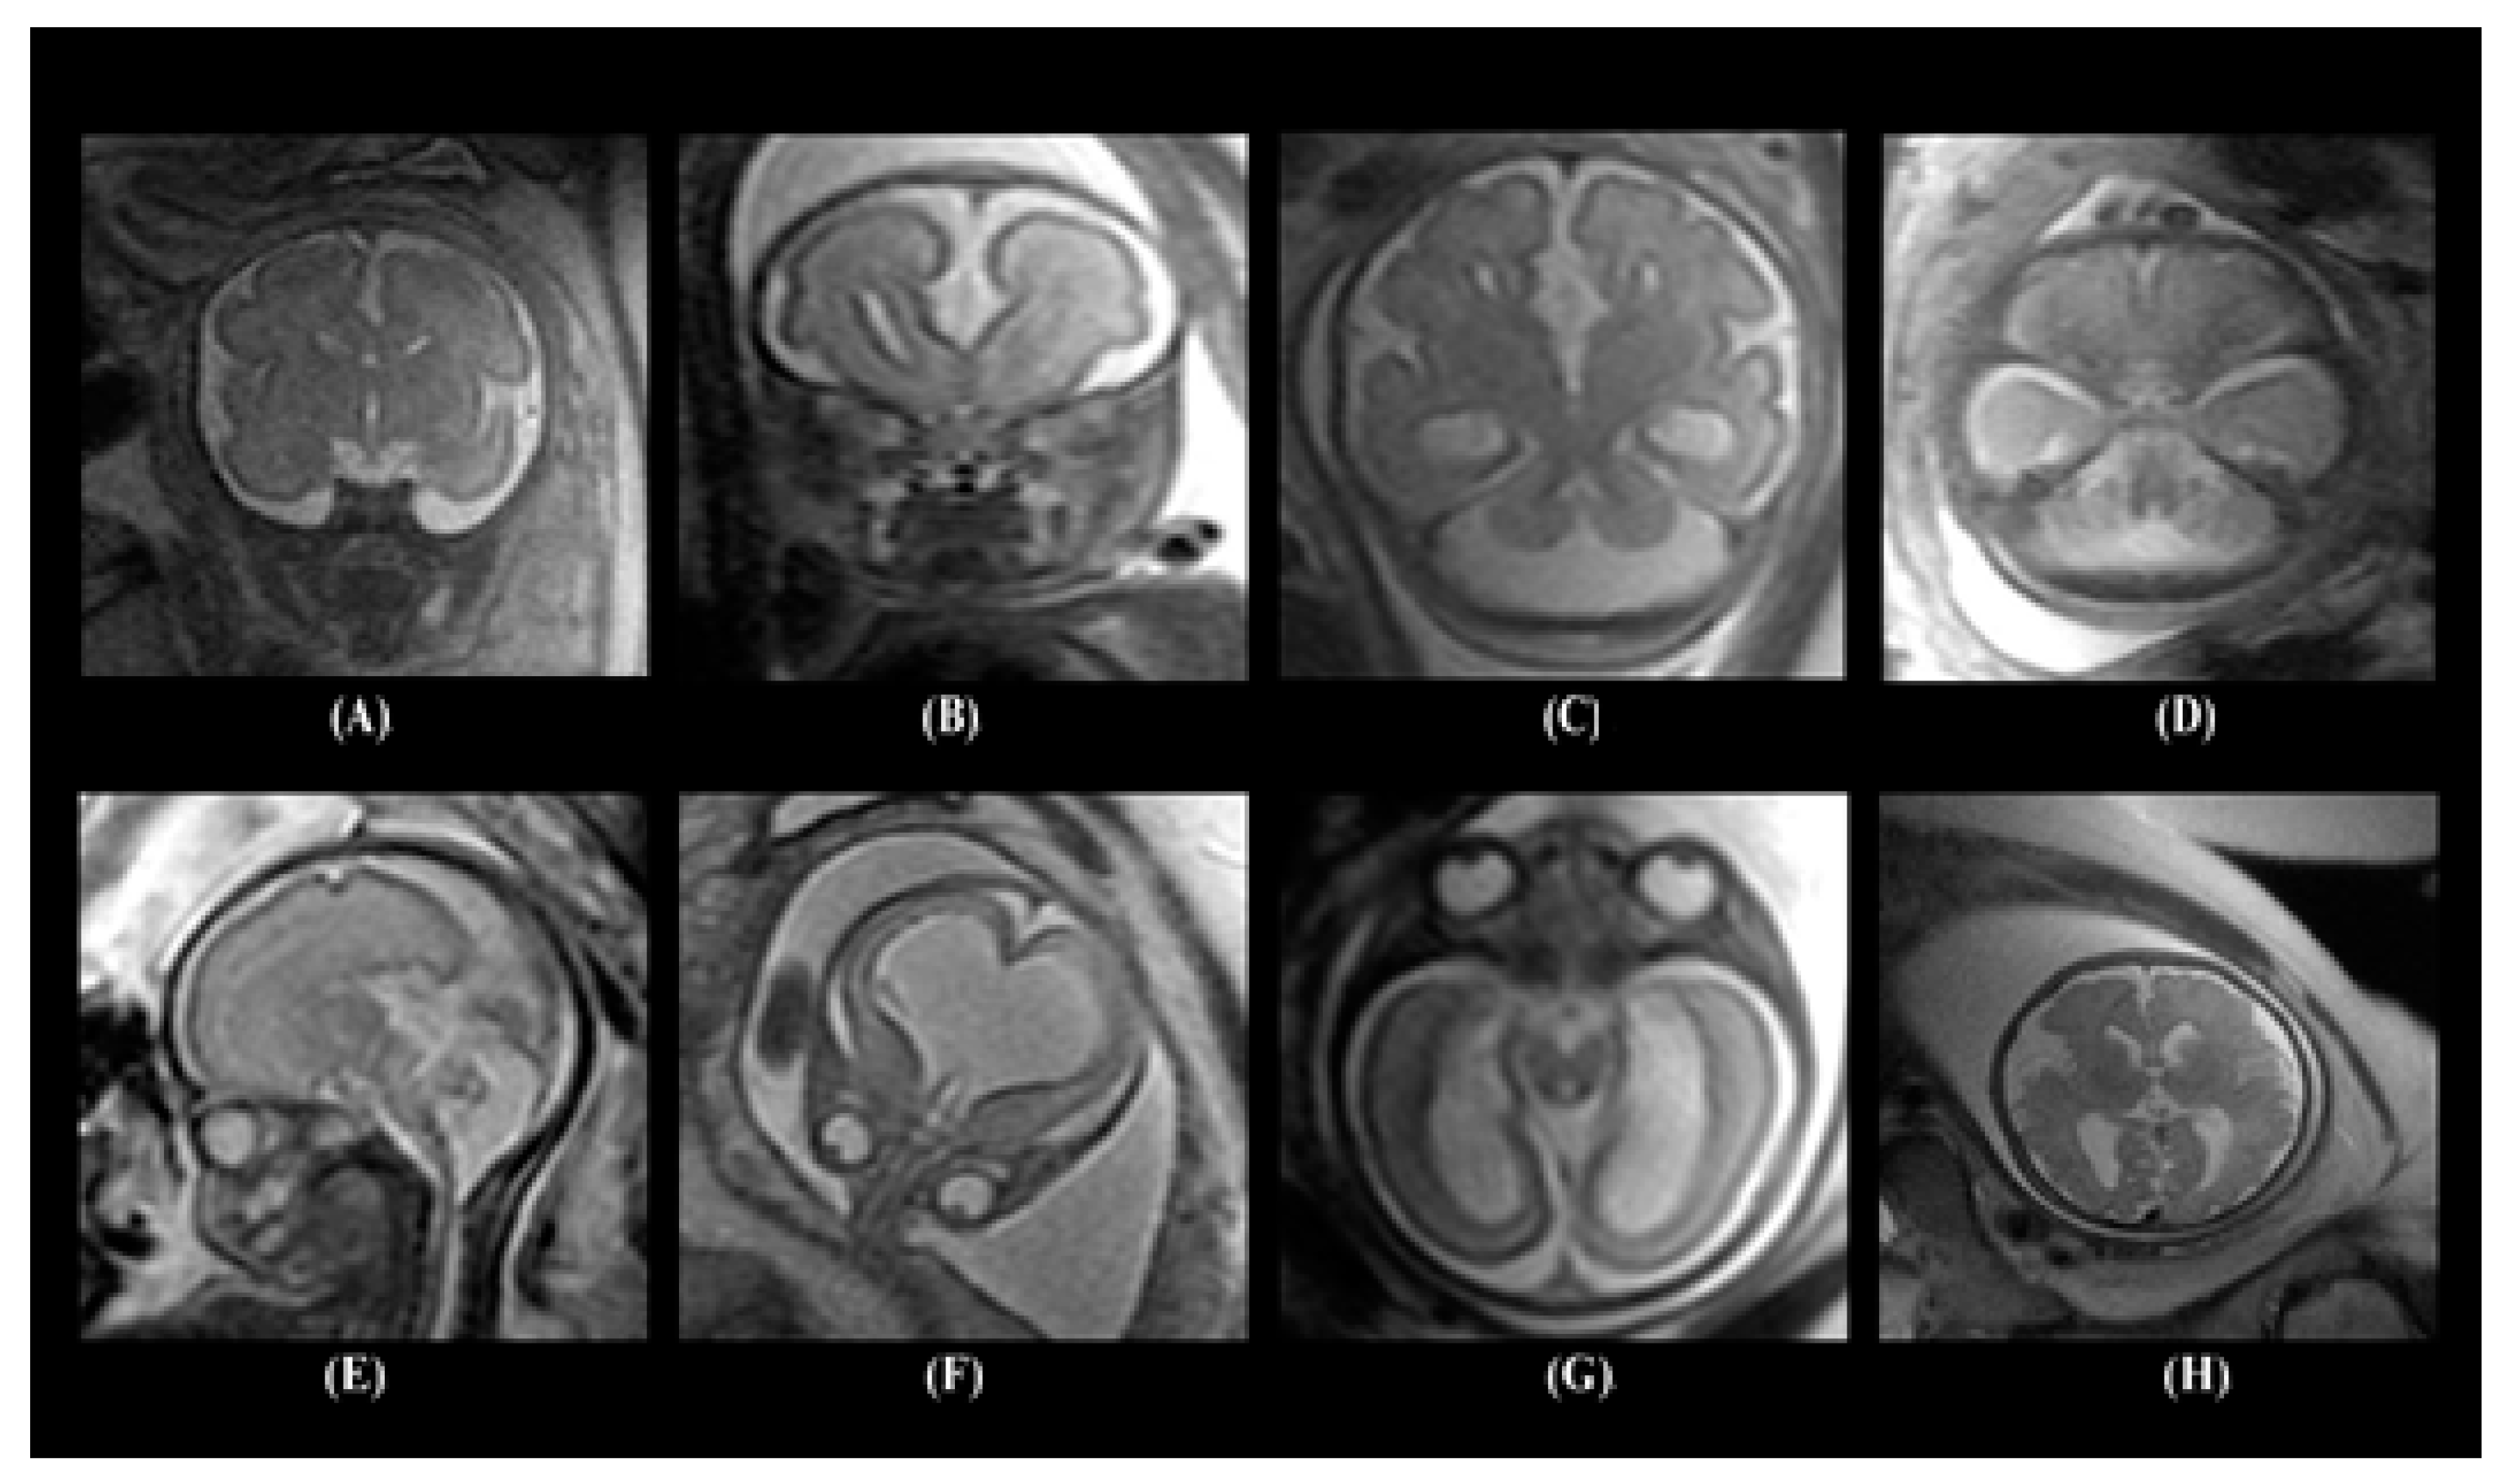

The dataset contained several types of neurodevelopmental disorders such as cerebellar hypoplasia, Dandy–Walker variant/malformation, colpocephaly, agenesis of the corpus callosum, mega-cisterna magna, agenesis of the septi pellucidi, and polymicrogyria. Figure 1 shows samples of the MRI images including healthy embryonic brains and brains with neurodevelopmental disorders.

Figure 1.

Images of different embryonic neurodevelopmental disorders: (A) normal embryonic brain, (B) agenesis of the corpus callosum, (C) colpocephaly, (D) mega-cisterna manga, (E) Dandy–Walker malformation, (F) agenesis of the septi pellucidi, (G) cerebellar hypoplasia, and (H) polymicrogyria.